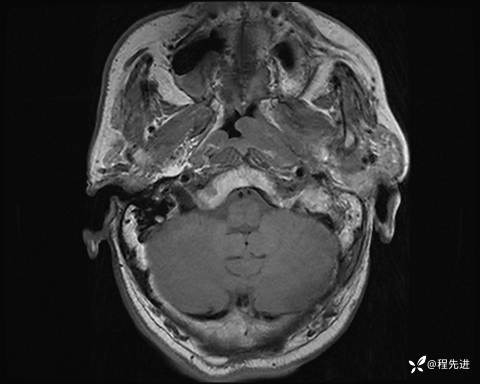

MRI平扫+增强:

T1: